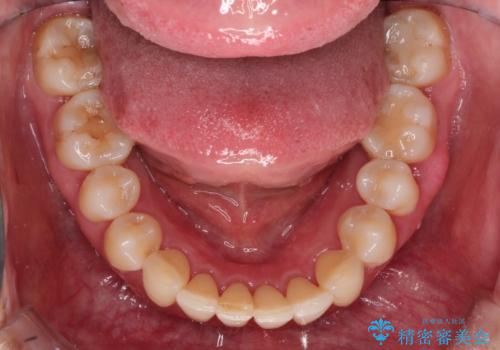

- 以前矯正をしていたが、わずかに後戻りをしてしまったのを主訴に来院されました。

装置はなるべくつけたくないとのことで、インビザラインにて治療することとなりました。

後戻りがわずかな場合は、期間も短くて済む場合があります。